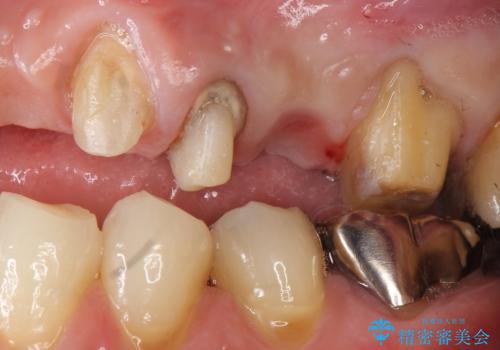

- ブリッジの支台歯であった左上の犬歯が折れたことを主訴に来院された患者様です。

犬歯は歯ぐきの奥深くまで割れており保存不可能な状態でしたが、どうしても抜きたくないとのことでした。

歯を牽引し健全歯質を歯肉縁上まで引き上げ、歯の保存を試みることにしました。

歯の牽引後、ブリッジの仮歯で保定しながら歯肉・骨の治癒を待ったのち、ブリッジによる補綴を行いました。

左上2欠損部の軟組織のボリュームが少なくポンティック部に食渣がたまりやすい歯肉形態であったため、歯槽堤増大術も提案しましたがご希望されませんでした。